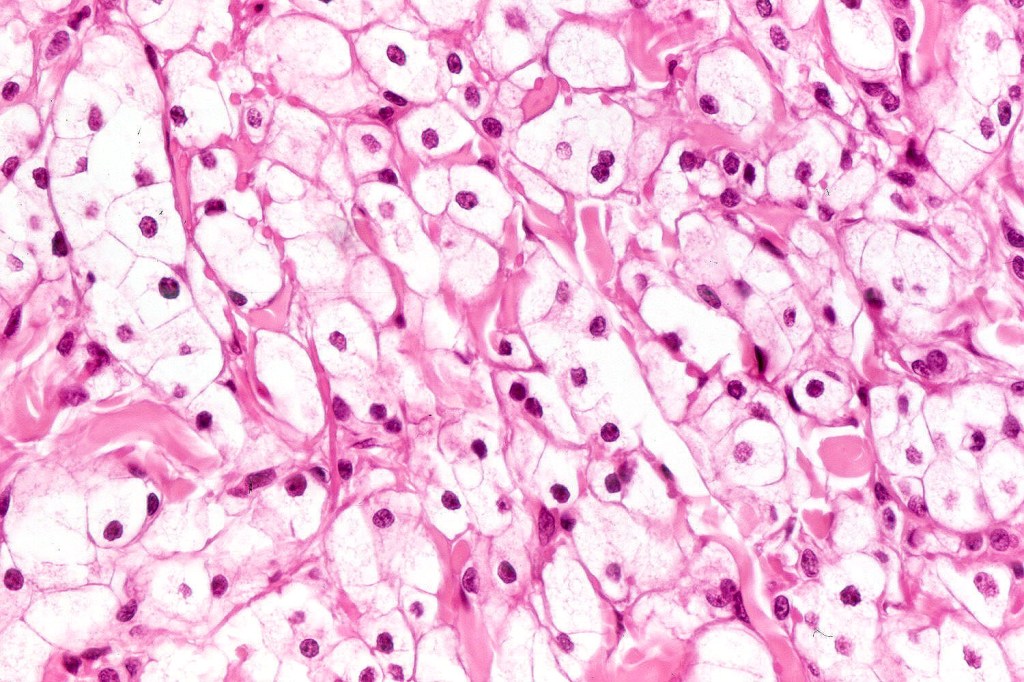

.Balloon cell nevs genrally has uniform, hyperchromatic nuceli (as opposed to the vesicular nuclei with prominent nucleoli) seen in melanoma. Mitoses are absent.(In my experience, balloon cell melanoma is more common than balloon cell nevus).

. In some balloon cell nevi, the microvesicles may result in nuclear scalloping reminiscent of a sebaceous tumor. In cases where there is real doubt, immunohistochemistry (S100), SOX10) will resolve the problem.

The importance of the entity is that it must always be distinguished from balloon cell melanoma. All cases should be scrutinized very carefully for pleomorphism and mitotic activiy before rendering a diagnosis of balloon cell nevus.